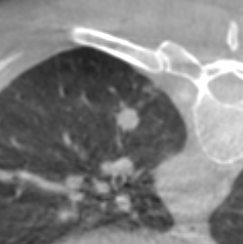

Sono stati inclusi 32 pazienti con 32 noduli polmonari inferiori ai 15 mm sottoposti ad agobiopsia percutanea mediante guida TC a fascio conico con braccio “a C” in un intervallo di 48 mesi da Gennaio 2018 a Dicembre 2021. Le procedure sono state eseguite con ago da biopsia automatico BARD MONOPTY © da 18 G. La biopsia è stata considerata diagnostica in presenza di esito istologico univoco, in assenza di necessità di ulteriori correlazioni anatomo-cliniche e/o in presenza di conferma istologica sul pezzo operatorio e/o con andamento clinico-radiologico al follow-up compatibile con l’istologia. Le complicanze principali della procedura comprendono emoftoe e PNX.

26 biopsie (81.3%) sono risultate diagnostiche. 17 (53.1%) sono risultate positive per malignità e 9 (28.1%) negative per malignità. Delle 6 biopsie non diagnostiche, 5 sono risultate lesioni maligne al follow-up e 1 paziente è stato perso al follow-up. Si sono verificati 18 PNX (56.3%) di cui 2 PNX (6.3%) con necessità di posizionamento di drenaggio toracico e 2 casi di emoftoe (6.3%) risolti con la variazione di decubito.

La TC a fascio conico é un valido supporto per l'agobiopsia percutanea di noduli polmonari di piccole dimensioni. I frustoli prelevati risultano diagnostici in un’ alta percentuale di casi con frequenza comparabile ai dati della letteratura riguardanti biopsie polmonari sotto guida TC spirale o TC a fascio conico. Il tasso di PNX è lievemente più alto che in letteratura, pur trattandosi per la maggiore di PNX di minima entità che richiedono esclusivamente il monitoraggio clinico.